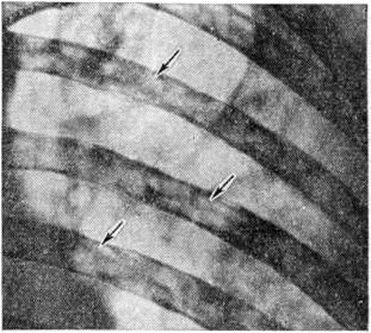

Повреждения ребер при миеломной болезни